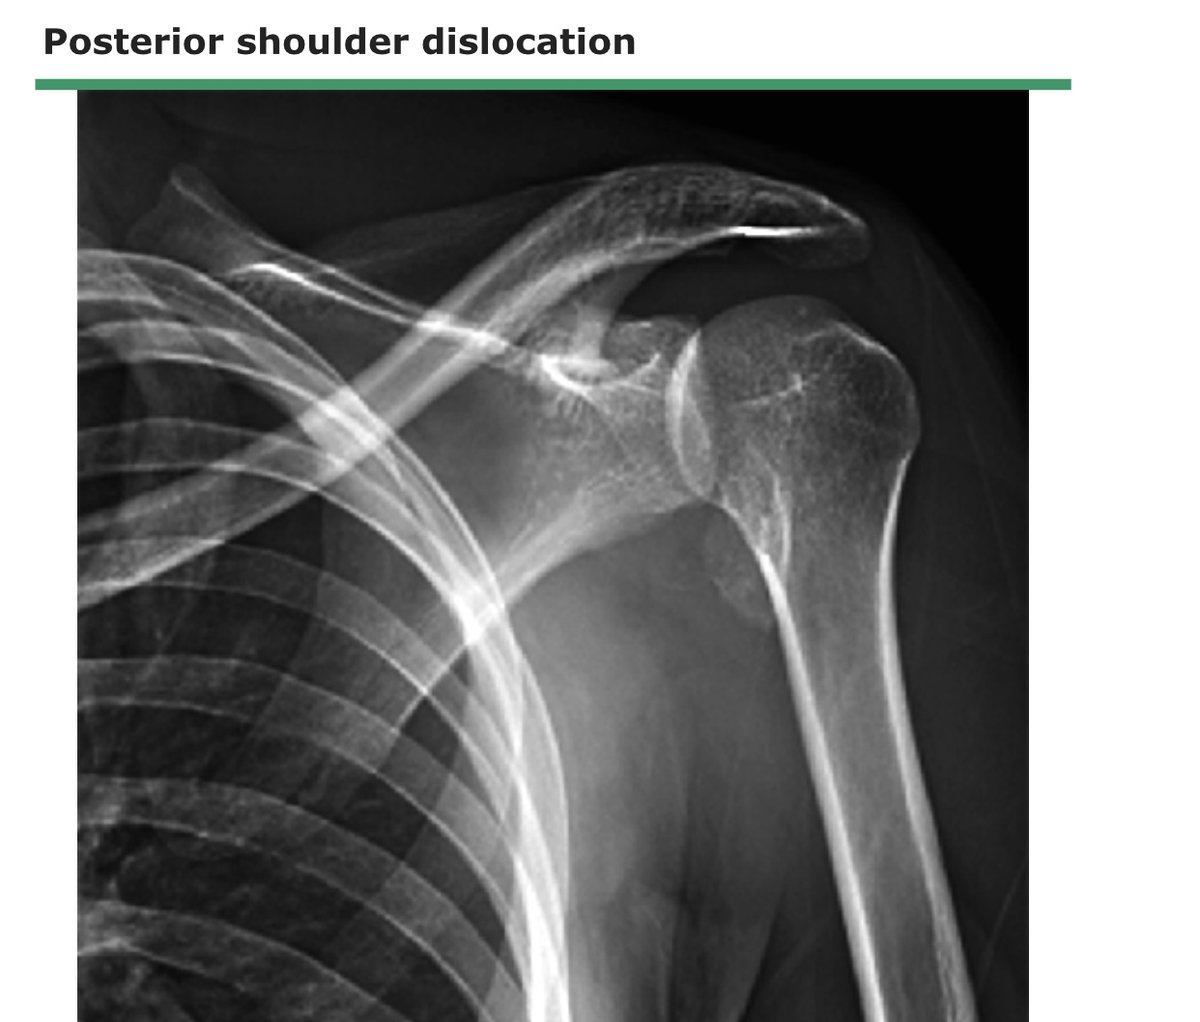

النوع الثاني :

نسبة حدوثه اقل ، طريقة الاصابة تكون في وضعية ( العضد قريبه من الجسم ، عظمة العضد ملتفه للداخل ) يحدث في حالات التشنج للجسم

العلامة المميزة له تسطح الجزء الامامي للكتف

يصاحبه غالبا كسر لرأس عظمة العضد او تهتك للغضروف او قطع وتر العضلة المدورة